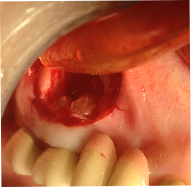

ΑΚΡΟΡΡΙΖΕΚΤΟΜΗ ΚΑΙ ΑΝΑΣΤΡΟΦΗ ΕΜΦΡΑΞΗ ΣΕ ΑΠΟΝΕΥΡΩΜΕΝA  ΔΟΝΤΙA ΚΑΙ ΑΦΑΙΡΕΣΗ ΚΥΣΤΕΩΝ